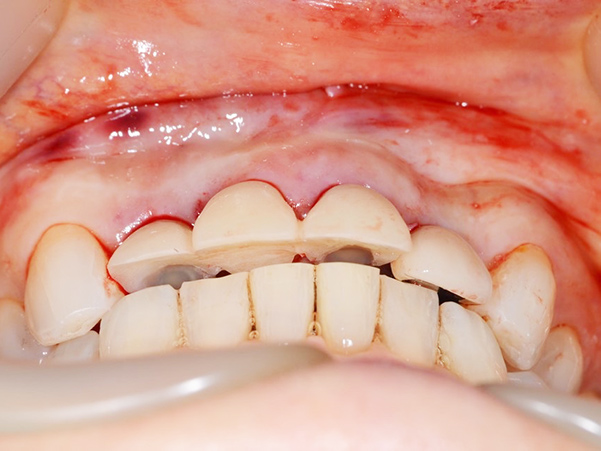

術後4ヶ月 仮歯の調整

1次手術時に製作した仮歯を外し、歯ぐきと周りの歯と調和するように仮歯の形を修正しました。本症例では骨造成を同時に行ったため、唇側の歯ぐきの幅が減ることなく、きれいな状態を保っています。

上部構造物装着

上部構造物を装着した状態です。まだ装着して日が浅いので、今後歯ぐきとの馴染みが十分ではありません。 インプラントは虫歯にはなりませんが、インプラント周囲炎になる可能性がありますので、今後は定期検診で確認し、健康な状態を維持していくよう努めていきます。